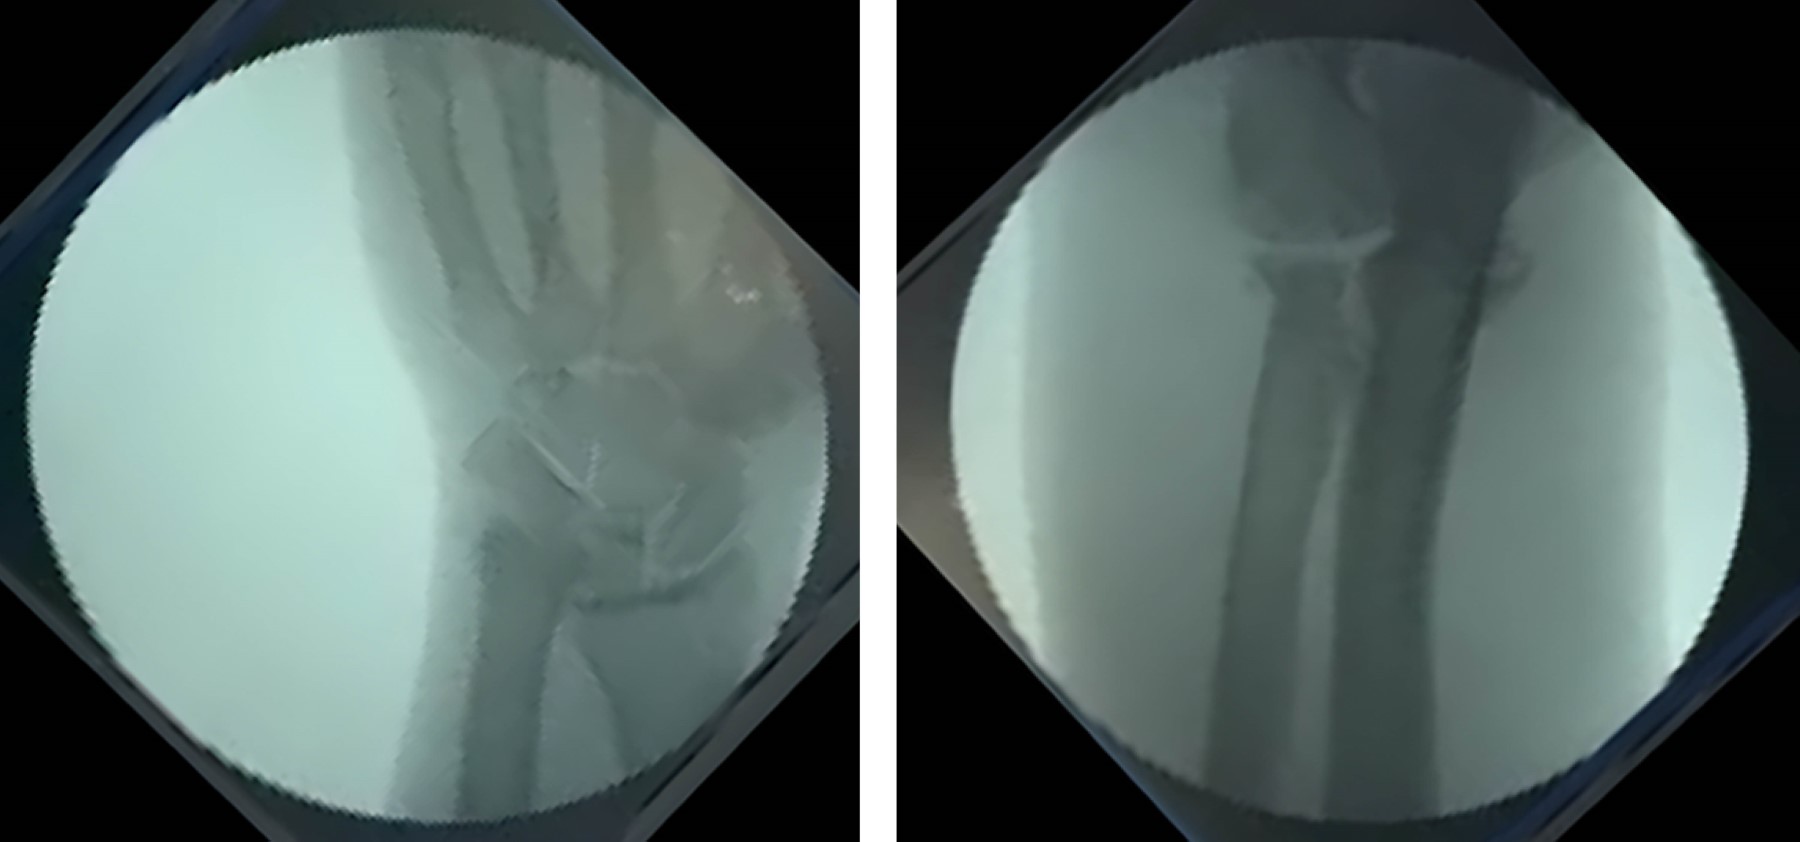

Introducción: el antebrazo puede considerarse como una articulación en sí misma donde interactúan el cúbito y el radio. Está constituida por la articulación radiocubital proximal (ARCP), la membrana interósea (MIO) con la banda medial como componente principal, y la articulación radiocubital distal (ARCD), que incluye el complejo fibrocartílago triangular (CFCT). La lesión de Essex-Lopresti (LEL) es una lesión compleja causada por una carga axial del antebrazo, que conlleva la disociación radiocubital longitudinal y la pérdida de estabilidad debido a la rotura de la MIO, la lesión de la ARCP con la cabeza del radio y lesión de la ARCD por afectación del CFCT. El diagnóstico precoz es crucial ya que el tratamiento de las lesiones crónicas plantea un importante desafío. Objetivo: describir la LEL crónica, revisar la literatura y compartir la experiencia de su tratamiento. Caso clínico: se describe el caso de un varón de 30 años que sufrió un accidente de moto en 2019. Diagnosticado inicialmente de fractura conminuta de cabeza radial derecha, fue tratado inicialmente mediante resección de la misma. El paciente visitó nuestro centro en 2023, la exploración clínica mostró dolor en muñeca y una protrusión dorsal de cúbito reductible pero inestable, sin dolor ni limitación de movimiento en el codo y antebrazo. Las pruebas complementarias, radiología simple y RMN, mostraron una varianza cubital positiva, una subluxación dorsal del cúbito a nivel de la muñeca y una lesión del CFCT, sin evidencia de ruptura aguda de la MIO. Se llevó a cabo un examen bajo anestesia y una evaluación fluoroscópica para examinar la estabilidad y el rango de movimiento del codo y la ARCD, así como la estabilidad longitudinal del antebrazo mediante tracción. Al no observarse inestabilidad longitudinal, se realizó una osteotomía de acortamiento del cúbito de 10 mm y se fijó con una placa y tornillos. De forma artroscópica, se observó la desinserción del CFCT y se reinsertó mediante una modificación de la técnica de Mantovani. Se inmovilizó con una férula de Münster. A los seis meses de seguimiento, tiene un EVA de 0 en codo y muñeca, y una flexión dorso/volar de 80º/80º, y un déficit de supinación/pronación de 10o/10o. Conclusiones: la LEL es una patología infrecuente pero desafiante para el cirujano. Las opciones terapéuticas incluyen diversas intervenciones quirúrgicas, siendo el acortamiento del cúbito con reparación del CFCT una opción viable en casos crónicos sin inestabilidad longitudinal.

Figura 4